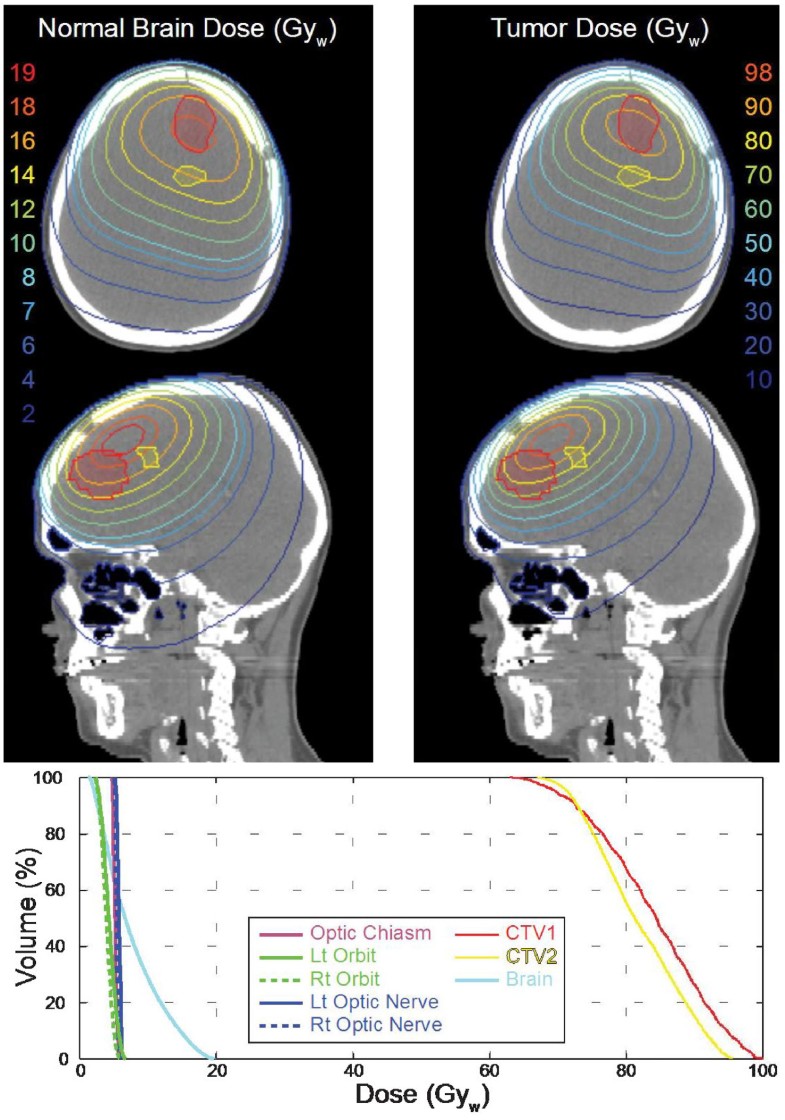

BNCT treatment plans are typically presented as total weighted doses, as shown in Figure 2 for tumor and normal tissue(s) and each is calculated separately for the entire dose grid using boron concentrations and weighting factors (RBEs) assumed for each tissue. The rationale for this approach is that the exact boundary of the tumor is unknown and that microscopic deposits of tumor extend well beyond the enhancing volume detectable by imaging. Generally, the tumor and tissue boron concentrations used for dose calculations in treatment planning are assessed as the product of blood boron concentrations measured for the patient at the time of irradiation and static tissue:blood boron concentration ratios determined in previous studies. For example, with BPA-fructose (BPA-F) common assumptions for tissue:blood boron concentration for tumor, normal brain, and skin are 3.5, 1.0, and 1.5. However, as shown in Figures 3 and 4, in cases where 18 F]BPA-F PET scans [64] are available, these data often are incorporated into the treatment plan and used to estimate the spatial distribution of boron in dose calculations. Application of 18 F]BPA-F PET data to dosimetry must, however, be interpreted with caution because of considerations such as the low spatial resolution and volume averaging effects of the PET scan as well as differences between the bolus injection of radiotracer and the large volume infusion of BPA-F that occurs over an extended time for treatment.

Figure 2

A three-field treatment plan for a brain tumor (GBM) patient calculated using the MiMMC treatment planning system. The prescription is a mean brain dose of 7.7 Gyw. Isodose contours calculated for tumor and normal brain are shown on axial and sagittal slices through the target volumes. The integral dose volume histograms (DVHs) summarize dosimetry for structures of interest including target volumes and organs at risk.